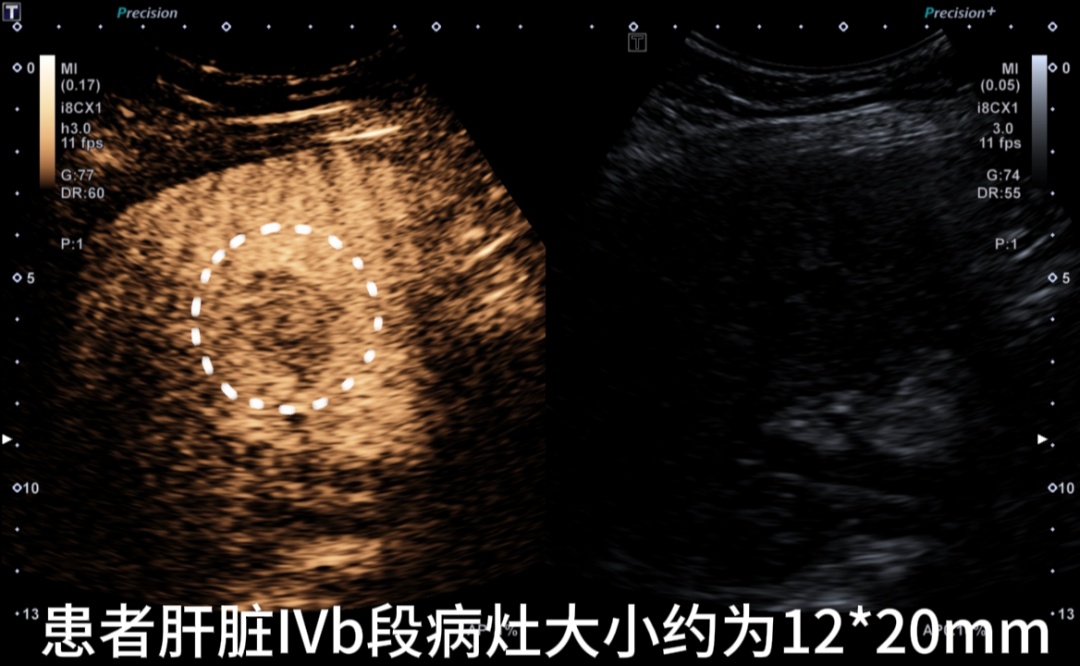

患者术前超声造影

IVb段病灶

IVa段病灶

两病灶内均无明显造影剂灌注,消融效果满意。